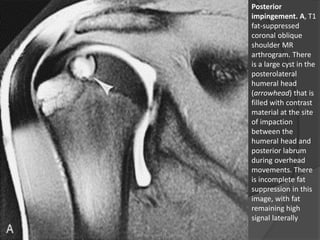

Posterior

impingement. A, T1

fat-suppressed

coronal oblique

shoulder MR

arthrogram. There

is a large cyst in the

posterolateral

humeral head

(arrowhead) that is

filled with contrast

material at the site

of impaction

between the

humeral head and

posterior labrum

during overhead

movements. There

is incomplete fat

suppression in this

image, with fat

remaining high

signal laterally